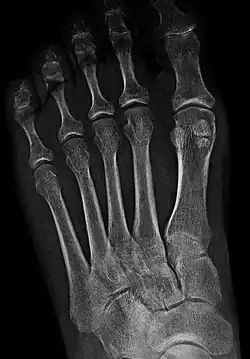

X-ray of the foot by dorsoplantar view, with most common accessory and sesamoid bones.[11]